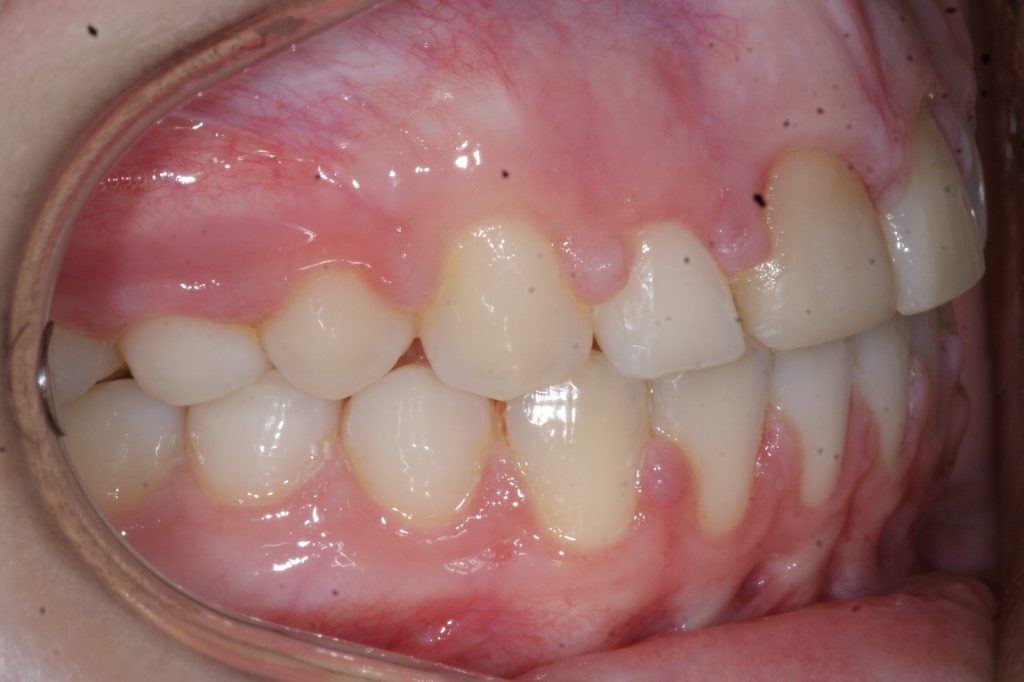

Correction d’une malocclusion de type Classe II division 1 avec excès d’espace aux 2 arcades.  Des appareils fixes (boîtiers) et une expansion palatine furent nécessaires pour améliorer ce sourire.  Traitement chez une adolescente, réalisé en 26 mois.